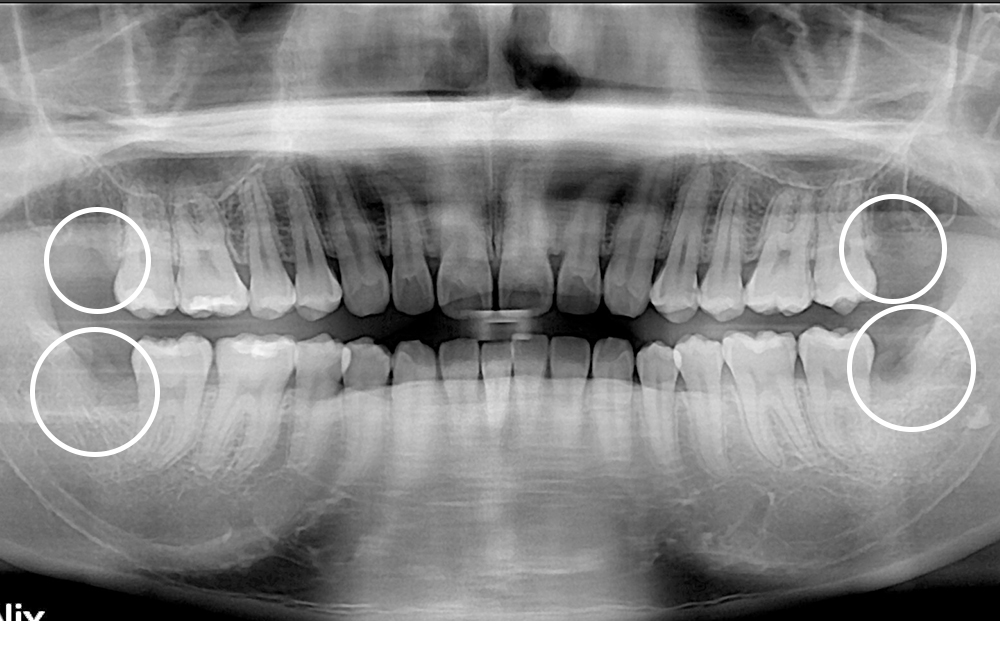

[사랑니] 매복 사랑니 발치

치료후 : 2019-09-11

세종치과는 구강악안면외과학 박사이신 원장님이 발치하는 치과입니다.